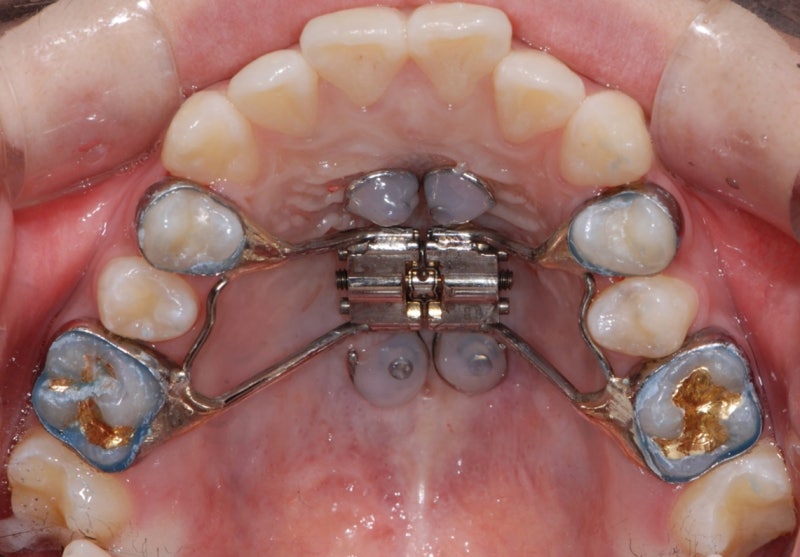

치아 교정 후 미묘하게 한쪽 눈이었던 것이 상당히 개선된 것을 확인할 수 있습니다. 아니, 무슨 치아 교정을 했는데 눈 크기와 위치가 바뀐다는 거야? 라고 물으실 수도 있겠지만, 지난 블로그 중 악궁 확장에 관한 시리즈의 글이 있으니 한번 참조해 보세요.위턱뼈는 눈 밑까지의 영역이기 때문에 위턱의 변화는 눈에까지 영향을 준다는 것을 저는 많은 치료에서 경험하고 있습니다. 진짜 신기하죠?치아를 보면 엄청나게 튀어나온 치아를 확인할 수 있습니다. 치아를 뽑고 교정을 하지 않을 수 없어요. 그런데 여기서 중요한 포인트를 하나!위는 먼저 악궁 확장을 통해 비염 코막힘, 얼굴 안면 비대칭, 한쪽 눈 등 위턱이 좁게 생기는 근본적인 문제를 해결하고 그 다음 발치 여부를 결정해야 합니다.아래에 앞니가 하나 없기 때문에 비발치보다는 발치를 선택하고 그 공간을 이용하여 치아를 배열하였습니다.위에서만 2개의 치아를 뽑고 치아교정을 했어요. 치아가 자라면서 공간이 없어졌습니다.치아 교정 완료 후 색상이 너무 노란색 앞니 2개는 라미네이트 치료를 실시하였습니다.색깔의 차이가 눈에 들어올 것입니다교정 완료 후 모양과 색을 개선했는데 잇몸이 내려가서 치아가 길어 보이지만 실제로 웃을 때는 치아가 노출되는 타입이 아니어서 문제가 없었습니다.좁은 악궁은 치아가 배열되기 어렵기 때문에 이것을 먼저 확장시킨 후 치아를 뽑아 교정했습니다.아래 역시 위와 같이 매우 좁은 악궁입니다. 이런 악궁이 혀가 들어가는 공간만큼은 반드시 넓어져야 합니다. 앞니가 하나 없어서 완벽하게 만들 수는 없지만 배열은 잘 완료되었습니다.제가 항상 강조하고 있지만 치아 교정이라는 것은 단순히 치열을 목적으로 하는 것이 아닙니다. 나무를 보기보다는 숲을 바라볼 수 있어야 하고 치아뿐만 아니라 우리 몸의 균형을 찾고 코막힘 비염과 같은 만성질환도 다뤄야 하며 한쪽 눈, 얼굴 안면 비대칭까지 매우 많은 효과를 볼 수 있도록 할 수도 있는 것이 치아교정의 위력입니다. 그래서 치과 선택이 중요한 거죠. 숲을 보는 곳에 가야하는 이유입니다.